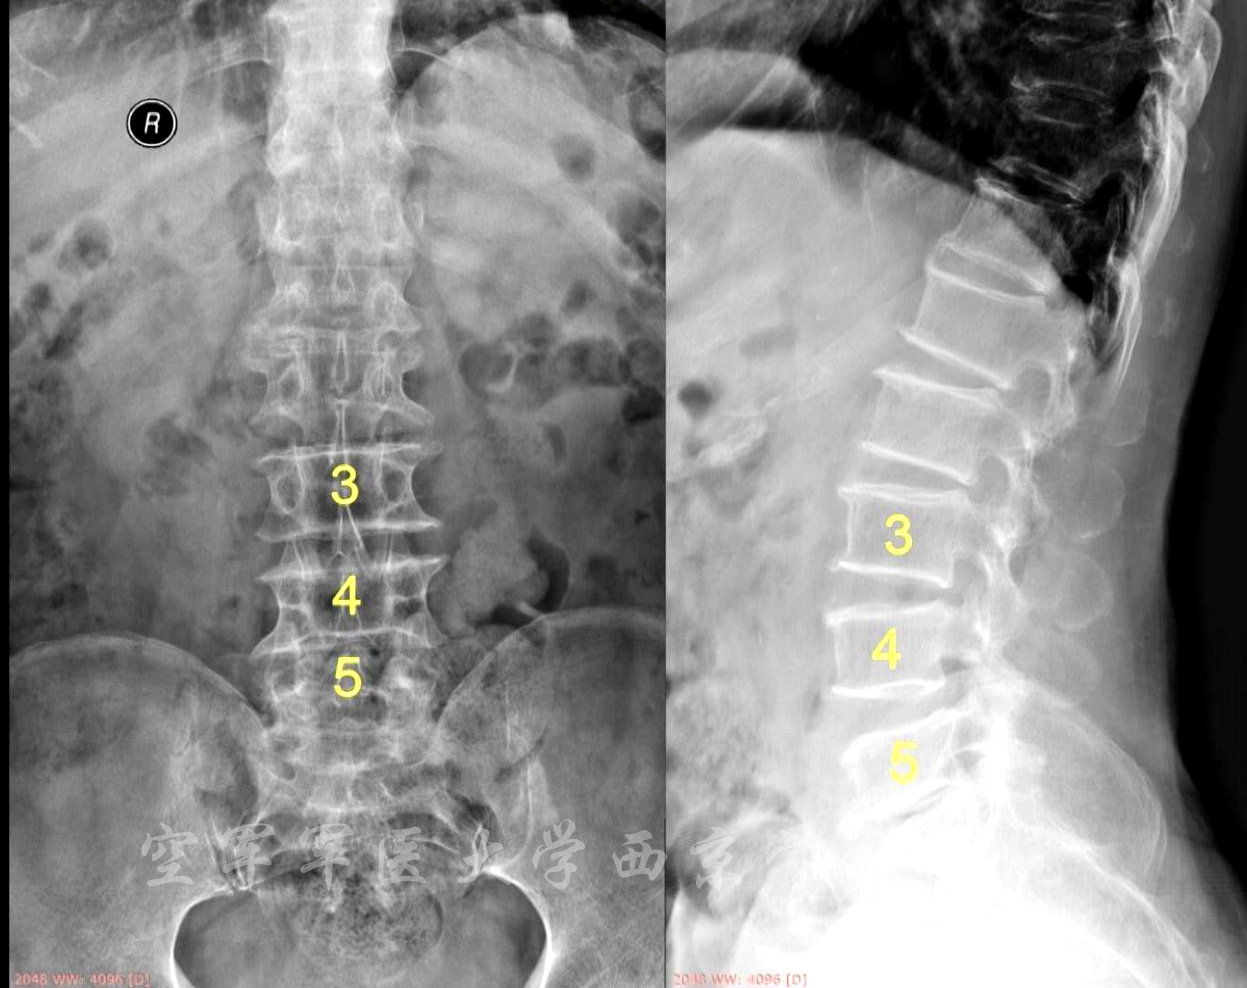

术前X线正侧位片